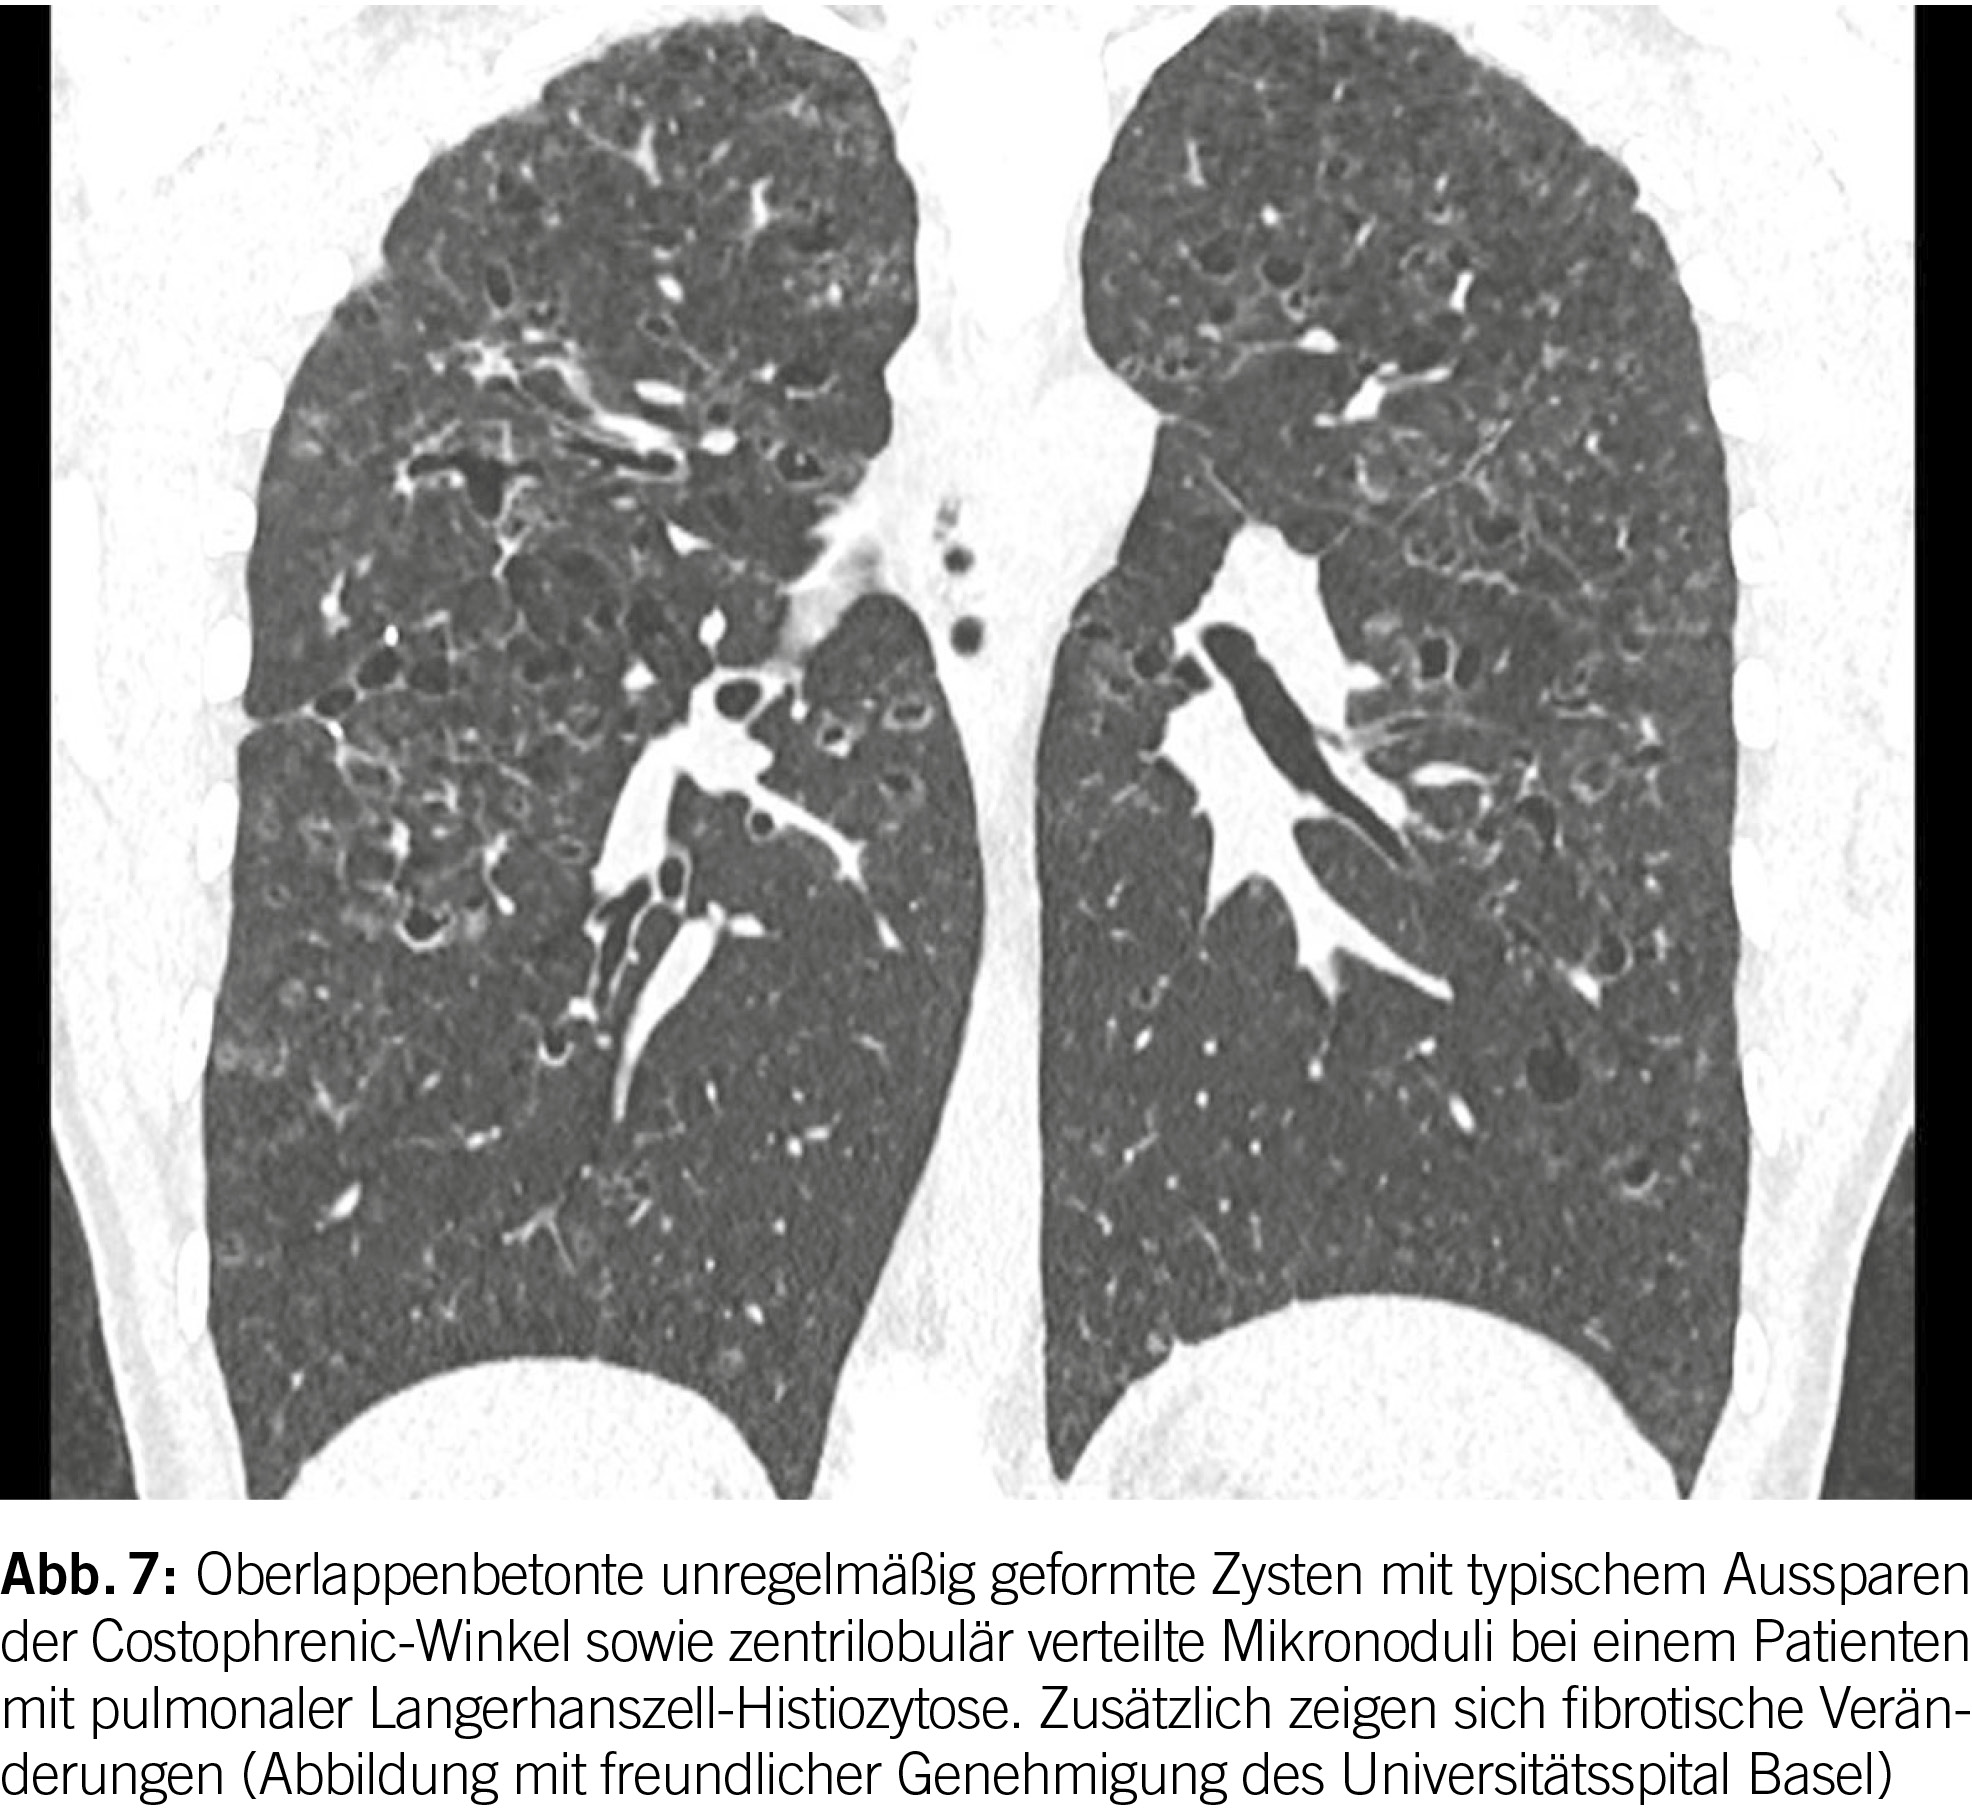

Die pulmonale Langerhans-Zell-Histiozytose (PLCH) ist eine systemische Erkrankung, die sich als diffuse zystische interstitielle Lungenerkrankung manifestiert und hauptsächlich junge Erwachsene betrifft, die rauchen. Obwohl die genaue Pathogenese der Krankheit noch diskutiert wird, besteht ein gut dokumentierter Zusammenhang mit Nikotinabusus als begünstigendem Faktor. Die Prävalenz des Zigarettenrauchens liegt bei über 90% der diagnostizierten PLCH-Patienten (18). Somatische Mutationen in den MAPK-Signalwegen, insbesondere BRAF V600E und MAPK2K1, sind in den meisten Fällen nachweisbar (19).

Die hochauflösende Computertomographie (HRCT) spielt eine entscheidende Rolle bei der Evaluation von PLCH. Das charakteristische Merkmal ist das Vorhandensein von diffusen Zysten und Noduli, die sich überwiegend in den mittleren bis superioren Bereichen der Lungen ansammeln, wobei der kostophrenische Winkel nicht befallen ist (20) (Abbildung 6). Die Noduli weisen oft eine schlecht definierte Form auf und messen typischerweise zwischen 2 und 10 mm.

Langerhans-Zellen sind spezialisierte dendritische Zellen, die eine entscheidende Rolle bei der Regulation der Schleimhautimmunität spielen (20). In der Pathologie von PLCH umfasst die initiale Läsion die Ansammlung aktivierter Langerhans-Zellen um die terminalen und respiratorischen Bronchiolen. Die Signale, die zur Aktivierung der Langerhans-Zellen führen, sind noch Gegenstand der Debatte, wobei das Rauchen einen prominenten Faktor darstellt (21). Die Langerhans-Zellen und die nachfolgende Rekrutierung von Entzündungszellen tragen zur Bildung von Noduli bei, die der Entwicklung von Remodeling der Atemwege und zystischen Veränderungen vorausgehen (19).